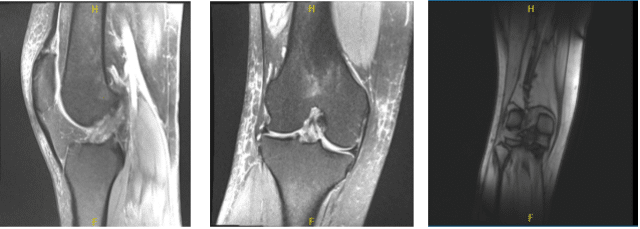

MRI-3T Right Knee non-contrast

A 29 year-old female patient seen in the office with right knee pain after MVA. She has a history of right knee injury with lateral meniscus tear, tricompartmental AO in 2018 following a dancing accident.

Examination of the lateral tibiofemoral compartment showed fraying and tearing of the lateral meniscus and the posterior horn as well as vertical tear of the body of the lateral meniscus. Debridement of lateral meniscus was performed.

There was a free edge tear of the anterior horn of the lateral meniscus also, which was debrided. Decision was made to repair the lateral meniscus considering that it was reducing very well.